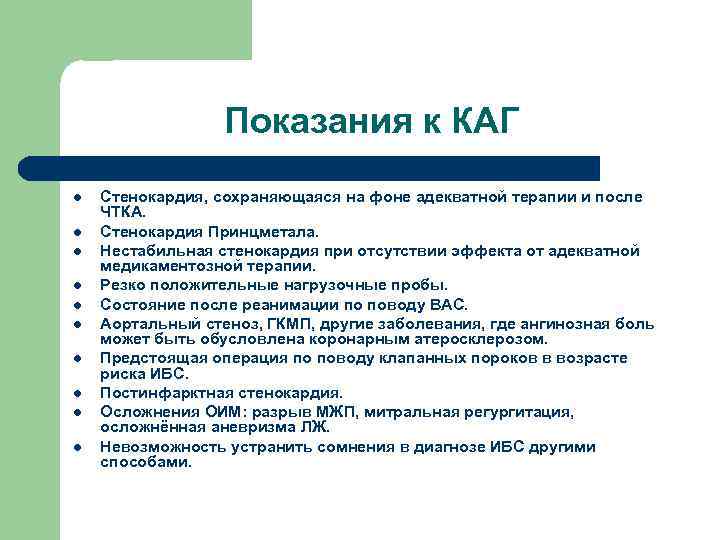

Показания к КАГ l l l l l Стенокардия, сохраняющаяся на фоне адекватной терапии и после ЧТКА. Стенокардия Принцметала. Нестабильная стенокардия при отсутствии эффекта от адекватной медикаментозной терапии. Резко положительные нагрузочные пробы. Состояние после реанимации по поводу ВАС. Аортальный стеноз, ГКМП, другие заболевания, где ангинозная боль может быть обусловлена коронарным атеросклерозом. Предстоящая операция по поводу клапанных пороков в возрасте риска ИБС. Постинфарктная стенокардия. Осложнения ОИМ: разрыв МЖП, митральная регургитация, осложнённая аневризма ЛЖ. Невозможность устранить сомнения в диагнозе ИБС другими способами.